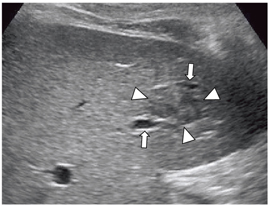

Fly Thruによる肝への応用で高いポテンシャルが期待されるのは,肝内門脈の病変である三次分枝の門脈腫瘍栓(VP1)の診断である。肝細胞がんにおいて,門脈の末梢に浸潤するVP1は,従来の画像診断では診断が不可能で,外科切除標本の病理検査が必要だった。例えば,肝細胞がんでは,超音波画像で病変に隣接して門脈枝や肝静脈枝が走行している場合,通常の超音波断層像では,門脈内にVP1があるかどうかは診断できない。高画質のBモード画像でも,血管が細く蛇行しているため,診断は困難である(図8)。造影超音波でも,血流があり閉塞していないことは確認できるが,VP1かどうかの診断には至らない。

![]() 図8 肝内門脈腫瘍栓の有無は高画質Bモード画像でも診断は困難 腫瘍(←で囲まれる)の近傍を走行する門脈枝(↑)は 蛇行するため内腔の描出が困難である。 |